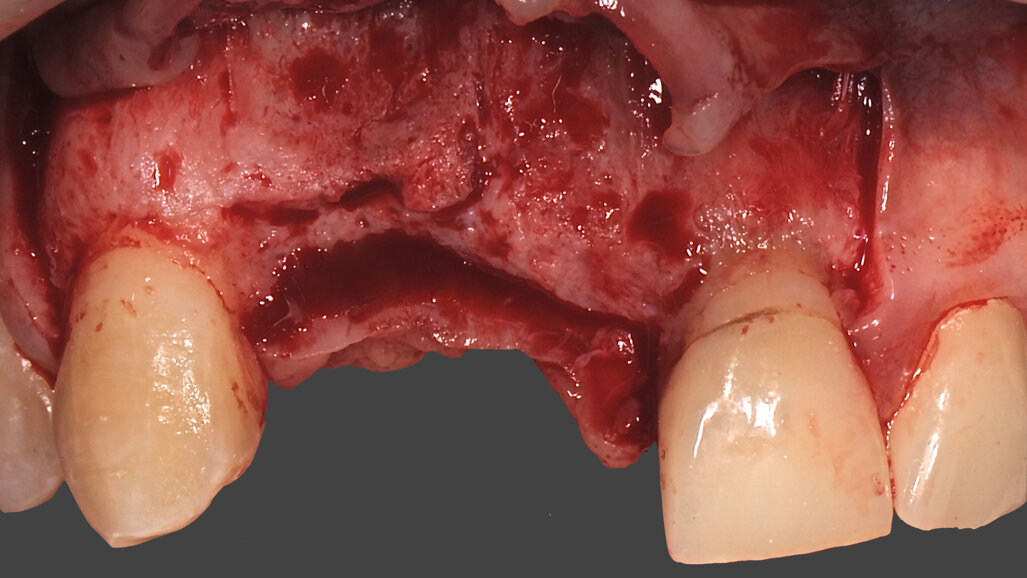

Il paziente, maschio caucasico di 28 anni, si presenta alla nostra osservazione in seguito a un incidente che ha provocato l’avulsione traumatica degli elementi 1.1 e 1.2 con conseguente riduzione dei volumi ossei della zona che, oramai, risulta parzialmente edentula. Sono inoltre presenti in corrispondenza degli elementi 2.1 e 2.2, anch’essi coinvolti nel trauma, due elementi provvisori in resina. La richiesta del paziente è quella di riabilitare la zona edentula con impianti e finalizzazione protesica da 1.2 a 2.2 con corone singole in ceramica1, 2. Dall’esame clinico si evidenzia una carenza di tessuto osseo sia in senso verticale (Fig. 1) che in senso orizzontale (Fig. 2). Si è deciso quindi che l’opzione terapeutica migliore per ottenere una buona rigenerazione ossea di tipo combinato, fosse quella di utilizzare una griglia in titanio customizzata3 in combinazione con un mix di osso bovino deproteinizzato (Geistlich Bio-Oss) e chips ossei prelevati nella zona operata tramite l’utilizzo di un un safe-scraper (Meta)4, il tutto ricoperto da uno strato di matrice Mucograft. Il protocollo operativo delle griglie in titanio customizzate Yxoss CBR prevederebbe l’utilizzo di una membrana in collagene come Geistlich Bio-Gide nella ricopertura della stessa. Personalmente in alcuni casi da me trattati ho deciso di sostituire la membrana in collagene con la matrice, sempre in collagene di origine suina ma in questo caso ricostituito, soprattutto nei settori estetici laddove è richiesta una maggiore quantità di tessuto cheratinizzato al fine di ottenere un risultato estetico migliore. Una volta esposto quindi il tessuto osseo (Figg. 3, 4), si è provveduto ad effettuare una serie di perforazioni a livello della corticale ossea al fine di favorire un regolare sanguinamento (Fig. 5): questo permetterà ai nostri materiali da rigenerazione di usufruire di una maggiore quantità di fattori di crescita, proteine morfogenetiche, ed ottenere quindi una loro migliore integrazione nel tempo.